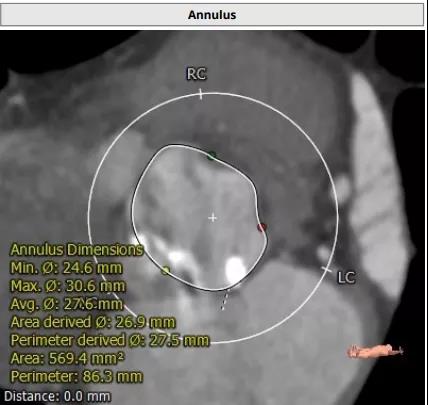

患者男性,67岁,活动后胸闷气促4年余。术前心脏超声提示先天性二叶式主动脉瓣畸形伴极重度狭窄及轻度反流,峰值流速7.1m/s,峰值压差200mmHg,平均跨瓣压差118mmHg,瓣口面积仅0.5cm2。CT评估显示主动脉瓣为Type I型二叶瓣,瓣环面积569.4mm2,测算直径26.9mm。左冠脉开口高度19.4mm,右冠脉开口高度18mm(紧邻右无冠窦交界)。该患者为重度肺气肿伴多发性肺大泡,重度肺功能不全、贫血、低血小板、虚弱,STS评分9.3%,属于外科手术高风险。

主动脉瓣瓣环 瓦式窦